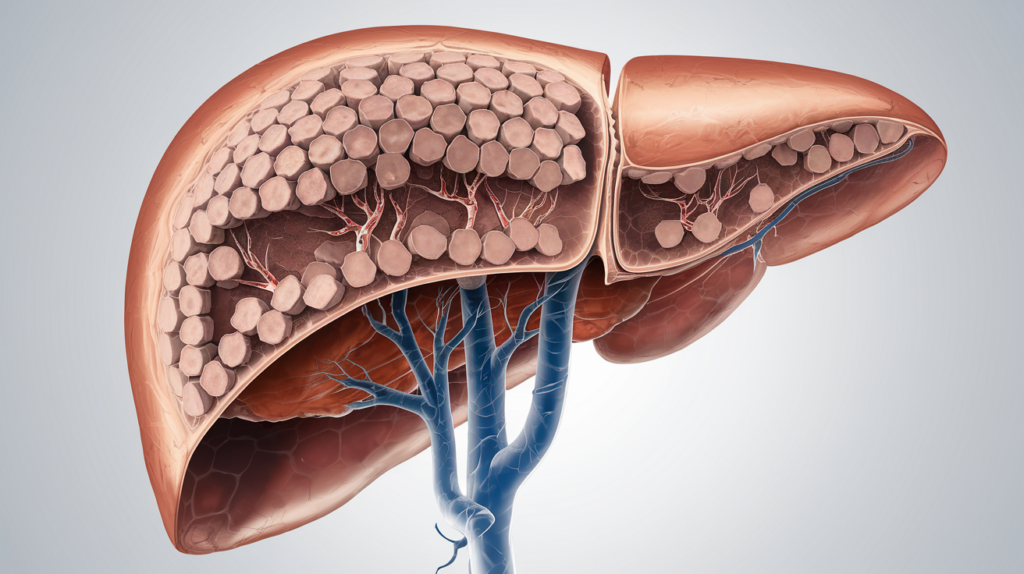

Understanding Liver Health and Function

Knowing how the liver works is important because it is involved in detoxifying the body, processing nutrients, and aiding digestion. It is responsible for filtering blood, producing essential proteins, storing nutrients, and supporting overall liver health.

The Role of the Liver in the Body

The liver is an organ that performs important jobs such as getting rid of toxins, processing substances, and producing proteins, all essential for health.

This important organ helps remove toxins and harmful substances from the blood, preventing them from building up and harming other organs.

It helps process nutrients from food, turning them into energy or storing them for later. Beyond these functions, the liver also synthesizes important proteins, including clotting factors and albumin, which are essential for blood health and fluid balance.

Its ability to regulate various biochemical processes underscores the liver’s importance in maintaining homeostasis, supporting liver function, and promoting overall bodily functions.

Common Liver Conditions and Risks

Common liver conditions such as fatty liver disease, hepatitis, cirrhosis, nonalcoholic fatty liver disease, alcoholic liver disease, and liver cancer pose significant health risks and can lead to liver dysfunction over time.